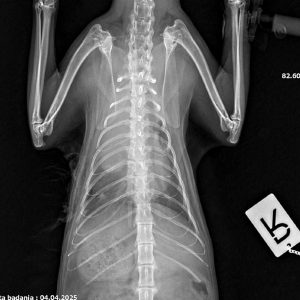

Zawiozłem ją z tego powodu do weterynarza. Została przeprowadzona diagnostyka i niestety, ten dzień stał się dla niej wyrokiem. Dla nas wszystkich. Małpeczka jest ciężko chora.Wykryto u Niej zmianę o charakterze guza. W celu potwierdzenia diagnozy należy przeprowadzić badanie tomografem komputerowym. Następnie powinno się wykonać torakotomię zwiadowczą z ewentualnym usunięciem zmiany lub pobraniem próbek do badania histopatologicznego. Koszt przeprowadzenia opisywanych procedur jest wysoki: 6 tysięcy zł.

Koszty te dla mnie obecnie są zbyt duże i na daną chwilę nie mam odpowiedniej kwoty. Operacja, tomograf, dalsze leczenie, dojazdy- przerastają moje możliwości. Dlatego proszę Was o wsparcie. W tym przypadku liczy się czas, czym prędzej uda się przeprowadzić operację, tym większe będą jej szanse na przeżycie i powrót do zdrowia. Zamieszczam zdjęcia rtg Małpeczki i opis badań.”